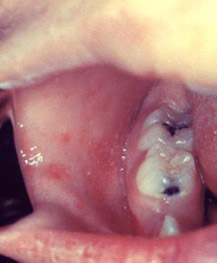

Signs and symptoms during the prodromal phase of measles develop one to two weeks after infection, with affected individuals typically experiencing increasing fever, a cough, runny nose and/or conjunctivitis.2Centers for Disease Control and Prevention. Measles Symptoms and Complications. https://www.cdc.gov/measles/signs-symptoms/index.html#cdc_symptoms_seek_help-complications.,7Katz SL, Hinman AR. Summary and conclusions: measles elimination meeting, 16-17 March 2000. J Infect Dis 2004;189(Suppl 1):S43-7. doi: 10.1086/377696. ,18Minnesota Department of Health. Measles Clinical Information. https://www.health.state.mn.us/diseases/measles/hcp/clinical.html#NaN. Affected individuals may develop a fever as high as 104° F, and may experience visual sensitivity to light and myalgia.4Chen SP, Glenn Fennelly. Measles. Medscape. Chief Editor: Steel RW. Updated May 2, 2024. https://emedicine.medscape.com/article/966220-overview. Two to three days after the onset of symptoms, Koplik spots appear on the buccal mucosa – usually opposite the second molars, presenting as tiny red spots with bluish-white centers that appear to superimpose the spots.19Koenig KL, Alassaf W, Burns MJ. Identify-isolate-inform: A tool for initial detection and management of measles patients in the emergency department. West J Emerg Med 2015;16:212-9. ,20Centers for Disease Control and Prevention. Clinical overview of measles. https://www.cdc.gov/measles/hcp/clinical-overview/index.html. Koplik spots are pathognomic for measles (specific to measles), and fade within one to two days of the rash developing.2Centers for Disease Control and Prevention. Measles Symptoms and Complications. https://www.cdc.gov/measles/signs-symptoms/index.html#cdc_symptoms_seek_help-complications. (Figure 1)

Images courtesy of the CDC.